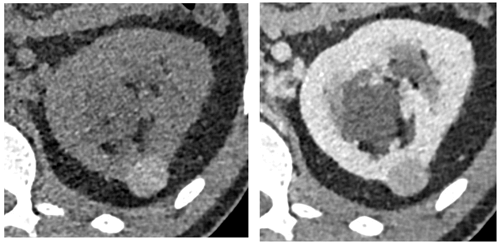

Due to the variability in the composition of cyst contents, attenuation values of hyperattenuating cysts on CT can be less than 70HU; hence without an unenhanced phase to measure contrast enhancement it is difficult to differentiate hyperattenuating cysts from solid enhancing lesions on a single portal venous phase examination (such as that performed for conventional abdominal CT). Incidental lesions with soft tissue attenuation on portal venous phase CT (20-100) therefore require careful comparison with previous available imaging or further characterisation with focused ultrasound, CT or MRI (Figure 9).

Figure 9:

A) Hyperattenuating cyst identified on lung cancer staging CT (42HU), portal venous phase. No enhancement on subsequent multi-phase CT.

B) Hyperattenuating cyst identified on lymphoma staging CT (38HU), portal venous phase.

C) Hyperattenuating lesion identified on CT Colonogram (42HU), portal venous phase. Further MRI characterisation revealed a benign cyst.

D) Hyperattenuating cyst identified on CT KUB for renal colic (38HU), unenhanced phase.